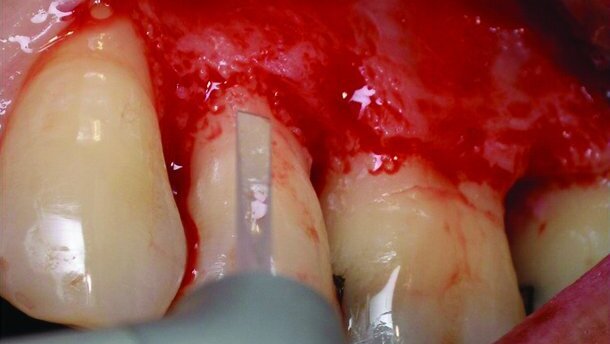

Un système en option d’alimentation par bouteille a été intégré dans l’appareil, pour une alimentation en solution saline stérile pendant la chirurgie. Les incisions intrasulculaire, palatines et buccales ont été effectuées avec une pointe de 600 μm sous anesthésie locale (Fig. 3). Un jet d’eau a été utilisé pour le refroidissement des tissus, tout au long de la procédure par laser erbium. Une pointe de saphir de 600 μm a été utilisée avec 200 mJ/35 Hz (= 7 W) en mode contact, à une profondeur intrasulculaire. Après le soulèvement du lambeau (Fig. 4) le tissu granulé a été enlevé par ablation et vaporisation, en utilisant une pointe de 1 300 μm, en mode sans contact, à une distance de 1 à 1,5 mm du tissu cible (Fig. 5). L’énergie utilisée pour cette procédure était de 400 mJ/20 Hz (= 8 W). Dans les embrasures étroites, où la pointe était trop large, la pointe de 1 300 μm a été remplacée par une pointe conique plus étroite (800 μm) et l’énergie a été réduite. Puisque le laser est émis par l’extrémité de la pointe et non par ses côtés, même lorsque le côté de la pointe « s’appuie » sur une autre dent pendant la libération du laser, la dent adjacente ne subit aucun dommage.